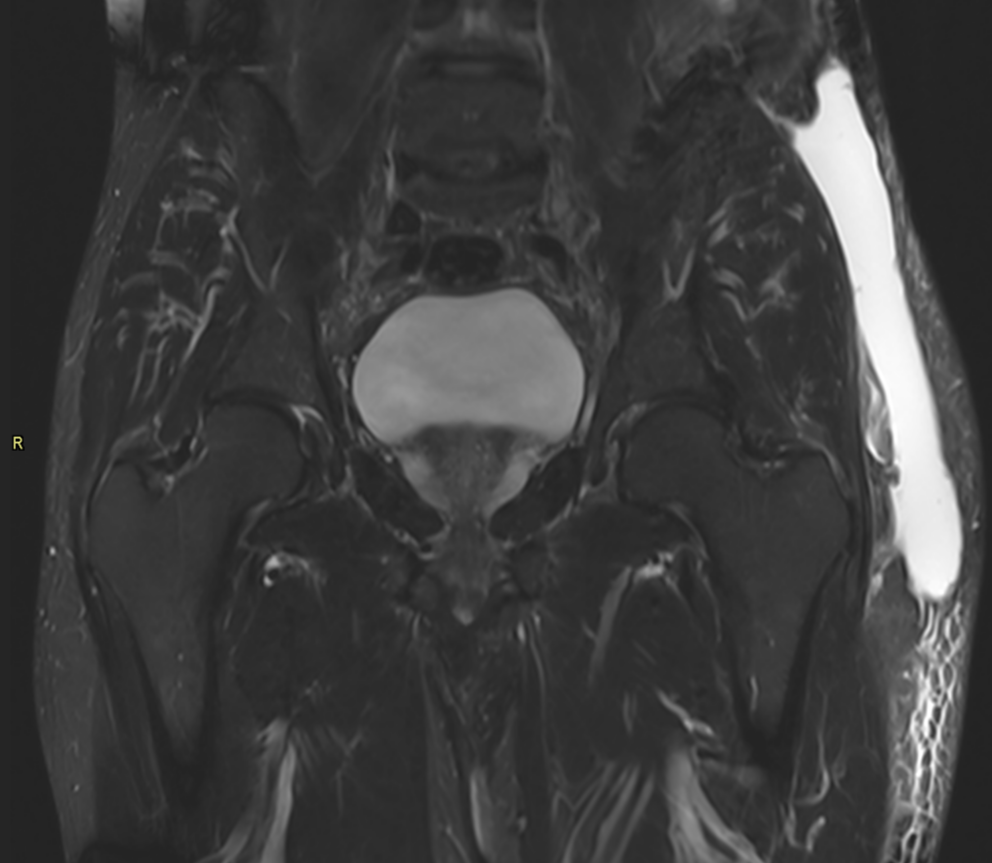

Morel Lavallée Lesion